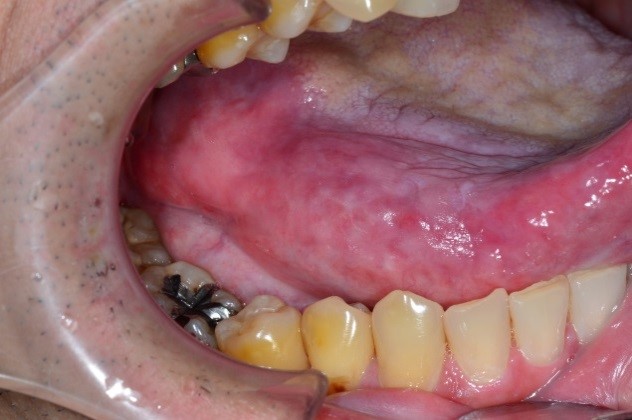

手術後

切らずに治せるので、食べる、咬む、飲み込む、しゃべるなどの様々な働きをできるだけ温存することができ、また顔や顎の変形を防ぐことができる非常に優れた治療法です。

治療中と治療後しばらく口内炎がでます。また、貧血などになる場合があります。治療期間が長くなることがあります。